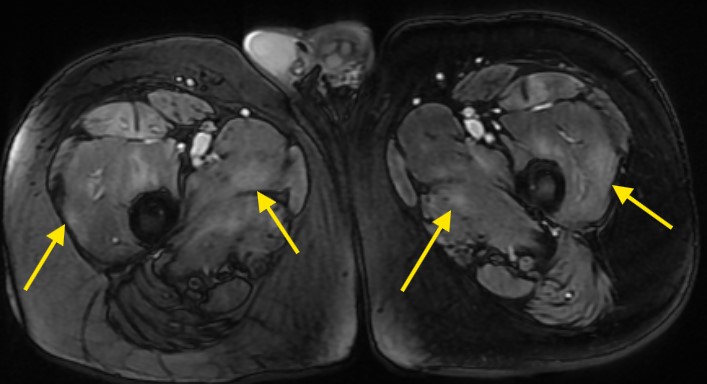

Based on elevated CK levels and a positive autoimmune serology, an initial diagnosis of polymyositis was considered. Magnetic resonance imaging

(MRI) of the thighs demonstrated diffuse muscle edema and T2-weighted hyperintensity involving the bilateral obturator externus, pectineus, iliopsoas, adductor and quadriceps muscles (Figure 2 and 3).

Figure 2: MRI scan of right thigh showing edema and inflammation of thigh muscles (yellow arrows).

Figure 3: MRI scan of bilateral thighs showing diffuse edema and inflammation of bilateral thigh muscles (Obturator externus, pectineus, iliopsoas, adductor muscles and quadriceps muscles) indicated by yellow arrows.

MRI also revealed a multifocal, patchy distribution of muscle edema, findings highly suggestive of inflammatory myopathy consistent with polymyositis. High-resolution computed tomography (CT) of the chest showed no evidence of interstitial lung disease. Electromyography (Table 3) demonstrated a myopathic pattern characterized by spontaneous activity, further supporting the diagnosis of inflammatory myositis. In the absence of muscle biopsy facilities, the patient was initiated on a three-day course of high-dose corticosteroids, followed by maintenance immunosuppressive therapy with azathioprine. Over a course of ne year the CK levels normalized, and the immunosuppressant therapy was stopped.